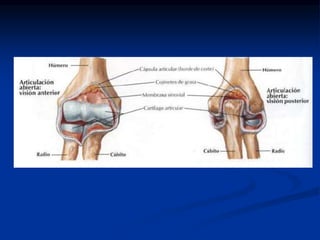

Las Articulaciones del Antebrazo

 El Antebrazo cuenta con varias articulaciones.

Entre ellas se encuentran:

 La Articulaculacion del Codo: La cual se compone

por las articulaciones:

1.-Articulación Humeroradial

2.-Articulación Radiocubital proximal

3.-Articulación Humerocúbital

 La Articulación Radio Cubital Distal

La Articulaculacion del Codo

 Articulación humeroradial: Se trata de

un tipo de articulación condílea o

esférica, sucede entre el cóndilo del

húmero y la

fosa de la cabeza del radio .

 Articulación Radiocubital proximal: Es

una articulación de tipo Trocoide ,

Localizada entre la Escotadura radial

del cubito (cavidad sigmoidea menor)

y la circunferencia articular del radio

Ligamento Anular.

 Articulación Humerocúbital: es una

tróclea aunque con un eje un poco

oblicuo , sucede entre la Tróclea del

húmero y la escotadura tróclear del

cubito (cavidad sigmoideo mayor)